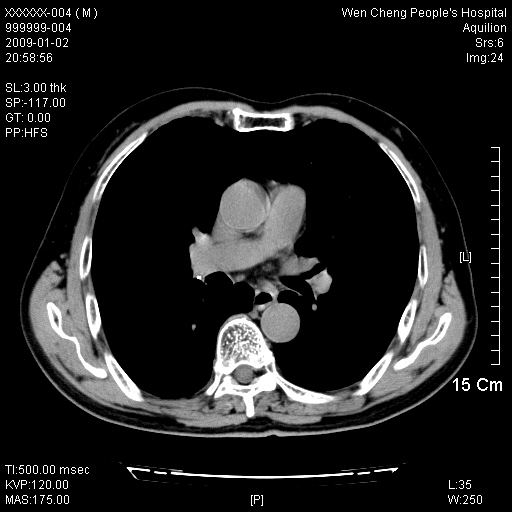

男性,73岁,有慢支病史,肿瘤系列标志物检验正常,血沉及血常规正常

右肺下叶背段小片状 磨玻璃样模糊影,内见血管及含气支气管像,支气管管壁增厚。考虑:慢性炎症!

1)不排除右肺下叶周围型肺癌可能;建议追踪复查。2)左右冠状动脉钙化。

右肺下叶背段小片状 实性与磨玻璃样影,内见血管及含气支气管像,支气管管壁增厚,边缘见长毛刺影。考虑:慢性炎症或肿瘤!建议抗炎治疗复查,密切观察随访!

右肺下叶片团状影内见扩张的含气支气管和支气管管壁增厚,其周有磨玻璃样模糊影和长毛刺。考虑慢性炎症可能性大。

2、右肺下叶片团状影内见扩张的含气支气管和支气管管壁增厚,其周有磨玻璃样模糊影和长毛刺。考虑周围型肺ca可能,结核不排。

3、左右冠状动脉钙化。

机化性肺炎 , 左右冠状动脉钙化。